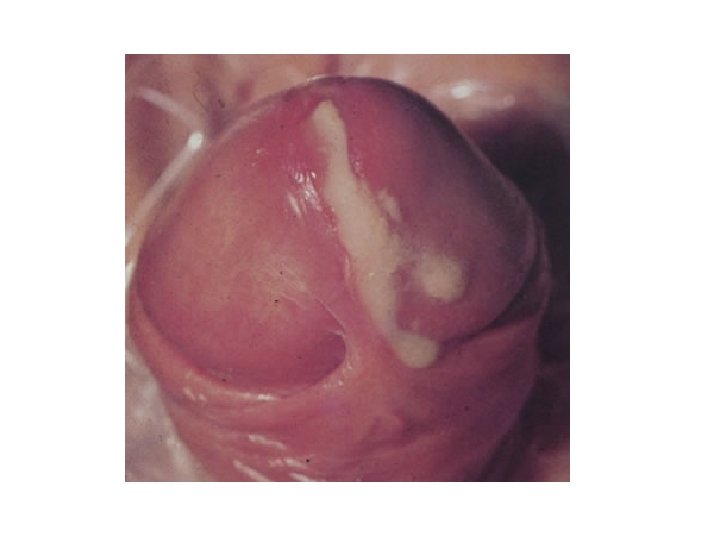

• Ka tri stade : primar sekondar terciar • Sifilisi primar eshte periudha e paraqitjes se ndryshimeve te para pas nje inkubacioni prej 21 ditesh , me paraqitjen e ulcus durum - varra(ulcera) e forte. Eshte nje lesion I vetem me diameter deri ne 2 cm me ngjyre te kuqe, me lokalizim te mashkujt ne prepucium te penisit , glans te penisit. Ndersa tek femrat ne cerviks , vagina , vulva vaginale , klitoris. • Sifilisi sekondar -fillon 2 -6 muaj pas infeksionit karakteriozhet me paraqitje te rozeilave sifilitke, condiloma lata, leukodermia , alopecia aoreale. • Sifilisi terciar qe perfaqeson periudhen destructive , qe mund te paraqitet pas muajve nga terheqja e sifilisit sekondar , kjo periudhe mund te zgjate edhe ne disa vite. Manifestohet me shfaqjen e ndryshimeve ne lekure dhe ne organe. • MJEKIMI • Antibiotic ( Penicilina)